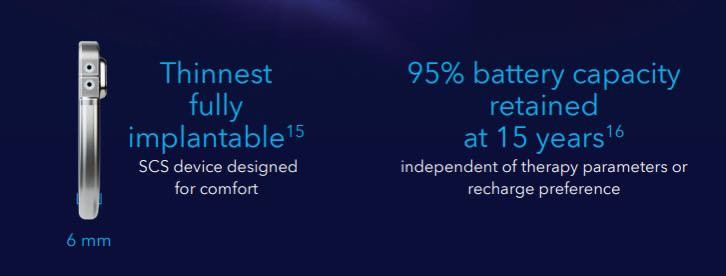

脊髓电刺激(spinal cord stimulation, SCS)

项目类型

器械质押区

起投金额

250000USDT

每日释放:0.95

释放周期:89 天

已购: 320

剩余: 0

Inceptiv

项目类型

器械质押区

起投金额

5500USDT

每日释放:0.8

释放周期:130 天

已购: 17818

剩余: 0